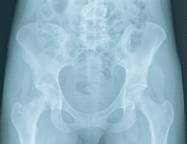

Chez les femmes, la décroissance de la masse osseuse débute quelques années avant la ménopause. La perte osseuse est alors de l'ordre de 1 à 2 % par an, pendant 8 à 10 ans, mais elle peut être plus considérable (5% par an). Passée cette période, la perte osseuse se stabilise autour de l'ordre de 0,5 - 1 % par an ; les rythmes de décroissance osseuse deviennent comparables chez l'homme et la femme. L'os spongieux est le premier touché par l'ostéoporose. Cet os se trouve en particulier au niveau des vertèbres. Lorsque la maladie évolue, les os longs s'amincissent dans leur partie externe, au niveau où l'os compact est plus présent. C'est pourquoi il existe des risques de fracture du col du fémur. L'ensemble du squelette peut être touché par l'ostéoporose, mais certains os sont plus vulnérables. Les conséquences de l'ostéoporose se font surtout sentir pour les os suivants : les vertèbres, les os du poignet, le col du fémur et les os de la mâchoire.

Les fractures du col du fémur. Elles ont lieu souvent après 75 ans et peuvent affecter l'autonomie de la personne âgée. La fracture du col du fémur peut être dramatique et causer le décès du patient dans l'année suivant l'accident (20 % des cas environ).

La pratique d'une activité physique permet de favoriser le remaniement osseux, et donc prévient les risques d'ostéoporose. Les articulations qui portent le corps (hanches, genoux) doivent être sollicitées. Quel que soit l'âge, il est donc important de pratiquer une activité physique régulière. Par exemple, 30 minutes de marche par jour sont conseillées. De même, chez les enfants, la pratique d'un sport favorise leur développement osseux et leur permet d'avoir un capital osseux satisfaisant.